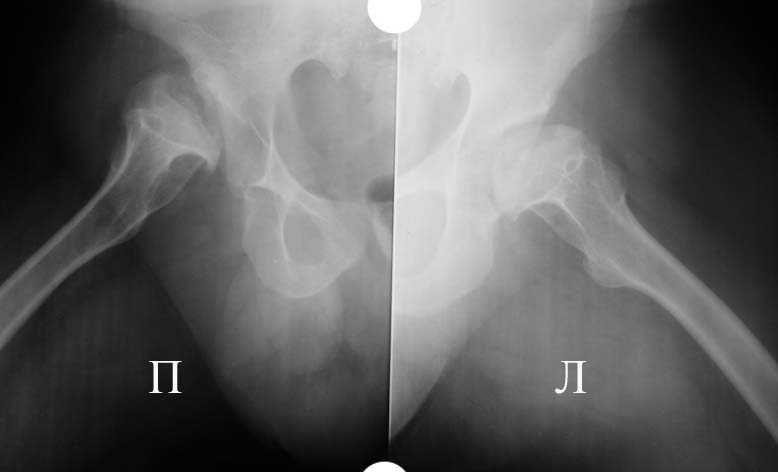

Аксиальная проэкция обоих т/б суставов

Алексей, качество Р-грамм не очень хорошее, канал виден только в одной плоскости (по-моему аксиальной), размеры кости не понятны. Думаю что можно подрыться без к/пластики, но головка то есть всегда. Канал не виден, ничего не могу сказать. Но наверно можно Аллоклассик с подстраховкой Вагнером.

Алексей, судя по снимкам, правый тазобедренный сустав нуждается в замене. Думаю, что получится поставить протез без дополнительных конструкций во впадину и особых ножек. Важным является диаметр канала. Надо по шаблонам оценить размер. Самые маленькие из известных мне ножек в России предсталены у De Puy (бесцементная 6), и новинка от BIOMET бесцементная диспластическая ножка.